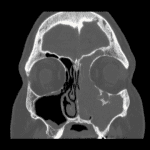

Age: 54

Sex: Male

Indication: Left nasal mass

Inverted Papilloma

- Inverted papilloma

Expansile mass in the left maxillary sinus with associated sinus wall remodeling and dehiscence and bulging into the nasal cavity and retroantral fat with obstruction of the left ostiomeatal unit. Hyperostosis about the left infraorbital canal is typical for inverted papilloma and represents the likely site of tumor origin.

Expansion of the medial aspect of the left frontal sinus with polypoid soft tissue markedly thinning the intersinus septum and bulging into the right frontal sinus, which could represent contiguous extension of the maxillary sinus mass versus separate mass/mucocele.

No definite dehiscence through the inner table of the calvarium.